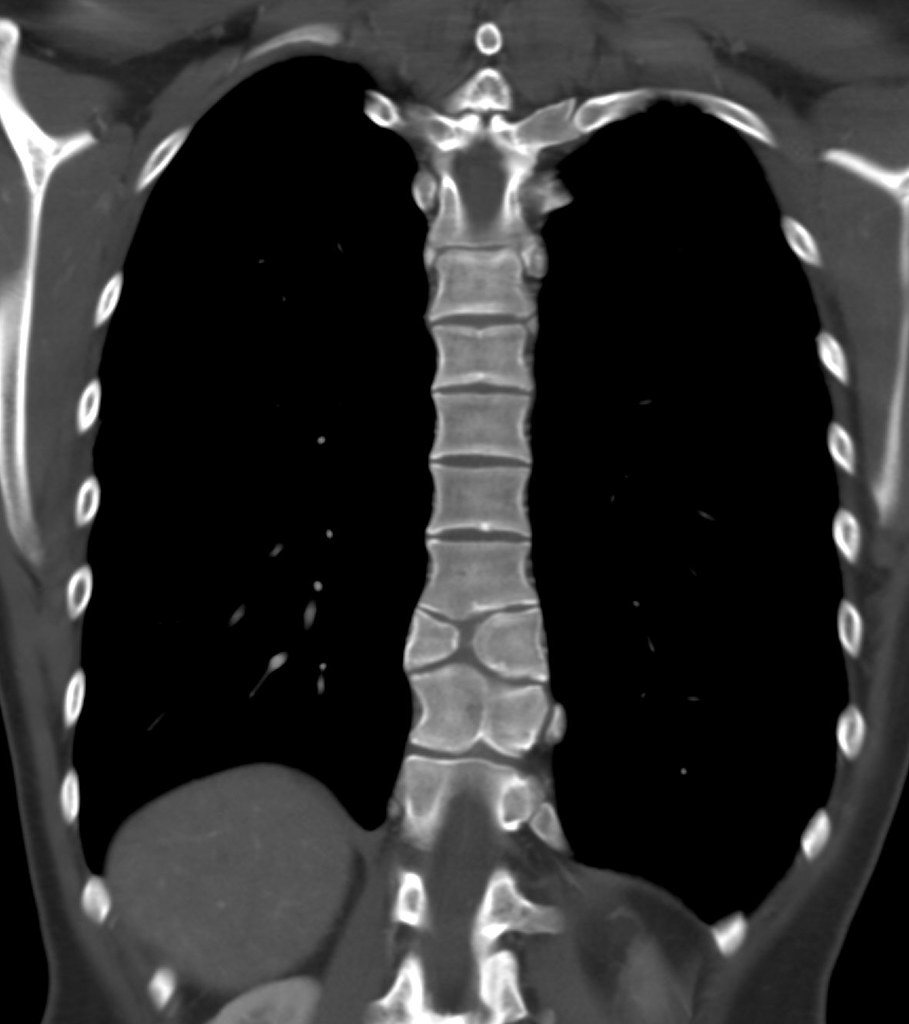

Butterfly Vertebrae . a butterfly vertebra is a vertebra with a midline sagittal cleft due to failure of fusion of the lateral halves of the. the butterfly vertebral defect is a rare congenital anomaly of the spine, which is. this study is the largest collection of butterfly vertebrae cases to date. a butterfly vertebra (bv) is a rare congenital anomaly resulting from a symmetric fusion defect. this article summarizes the demographics, clinical presentations, and conditions associated with butterfly vertebrae, a rare. the butterfly vertebra is a type of vertebral anomaly that results from the failure of fusion of the lateral halves of the vertebral. isolated butterfly vertebrae may be associated with back pain, disc.

a butterfly vertebra (bv) is a rare congenital anomaly resulting from a symmetric fusion defect. the butterfly vertebral defect is a rare congenital anomaly of the spine, which is. isolated butterfly vertebrae may be associated with back pain, disc. this study is the largest collection of butterfly vertebrae cases to date. a butterfly vertebra is a vertebra with a midline sagittal cleft due to failure of fusion of the lateral halves of the. the butterfly vertebra is a type of vertebral anomaly that results from the failure of fusion of the lateral halves of the vertebral. this article summarizes the demographics, clinical presentations, and conditions associated with butterfly vertebrae, a rare.

Butterfly Vertebrae this study is the largest collection of butterfly vertebrae cases to date. a butterfly vertebra (bv) is a rare congenital anomaly resulting from a symmetric fusion defect. this article summarizes the demographics, clinical presentations, and conditions associated with butterfly vertebrae, a rare. the butterfly vertebra is a type of vertebral anomaly that results from the failure of fusion of the lateral halves of the vertebral. the butterfly vertebral defect is a rare congenital anomaly of the spine, which is. isolated butterfly vertebrae may be associated with back pain, disc. this study is the largest collection of butterfly vertebrae cases to date. a butterfly vertebra is a vertebra with a midline sagittal cleft due to failure of fusion of the lateral halves of the.